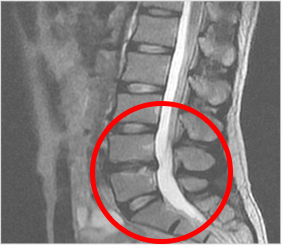

척추뼈 사이사이의 물렁뼈로서 쿠션 역할을 하는 구조를 말하며 추간판을 이루는 섬유테의 손상이나 내부의 수핵이 밀려 나오며 추간판 바깥쪽의 신경주위에 염증을 일으키거나 신경을 압박함으로써 통증을 유발할 수 있습니다. 이러한 질환을 통상 허리디스크라고 부르곤 합니다.

관련된 병명으로는 요추추간판탈출증, 추간판내장증, 퇴행성 디스크 등이 있습니다.

추간판의 손상 정도, 탈출 정도, 신경 압박 여부에 따라 증상은 허리통증, 골반통, 하지 방사통, 하지의 감각 이상, 근력저하, 대소변장애 등 다양한 증상을 보일 수 있습니다. 조기에 진단받고 상태에 맞는 치료 또는 관리가 필요하며 방치할 경우 일상생활의 불편함과 병이 악화함으로써 시간적, 경제적 손실을 일으킬 뿐 아니라 심각한 장애를 가져올 수도 있습니다.

디스크의 진행단계

요추 추간판 수핵탈출증의 단계

팽륜

돌출

탈출

전위

요추간판 수핵탈출증은 대개 한쪽 다리로 통증이 느껴지고 발까지도 같이 아프게 됩니다. 허리에는 증상이 없이 다리만 저리고 아픈 증상이 나타나기도 합니다.